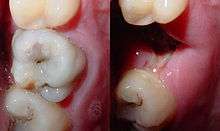

A person experiencing caries may not be aware of the disease.[10] The earliest sign of a new carious lesion is the appearance of a chalky white spot on the surface of the tooth, indicating an area of demineralization of enamel. This is referred to as a white spot lesion, an incipient carious lesion or a "microcavity".[11] As the lesion continues to demineralize, it can turn brown but will eventually turn into a cavitation ("cavity"). Before the cavity forms, the process is reversible, but once a cavity forms, the lost tooth structure cannot be regenerated. A lesion that appears dark brown and shiny suggests dental caries were once present but the demineralization process has stopped, leaving a stain. Active decay is lighter in color and dull in appearance.[12]

As the enamel and dentin are destroyed, the cavity becomes more noticeable. The affected areas of the tooth change color and become soft to the touch. Once the decay passes through enamel, the dentinal tubules, which have passages to the nerve of the tooth, become exposed, resulting in pain that can be transient, temporarily worsening with exposure to heat, cold, or sweet foods and drinks.[13] A tooth weakened by extensive internal decay can sometimes suddenly fracture under normal chewing forces. When the decay has progressed enough to allow the bacteria to overwhelm the pulp tissue in the center of the tooth, a toothache can result and the pain will become more constant. Death of the pulp tissue and infection are common consequences. The tooth will no longer be sensitive to hot or cold, but can be very tender to pressure.